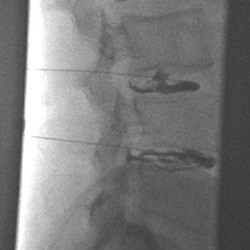

The upper X-ray image shows a discography of a herniated disc with a leakage of a contrast agent into the spinal canal (lower disc). The contrast agent is injected through fine needles. It is visible as a dark/black fluid. The lower CT image shows a reconstructed spine for the better evaluation of even small tears of a vertebral disc. The contrast agent is visible as a bright/white liquid.